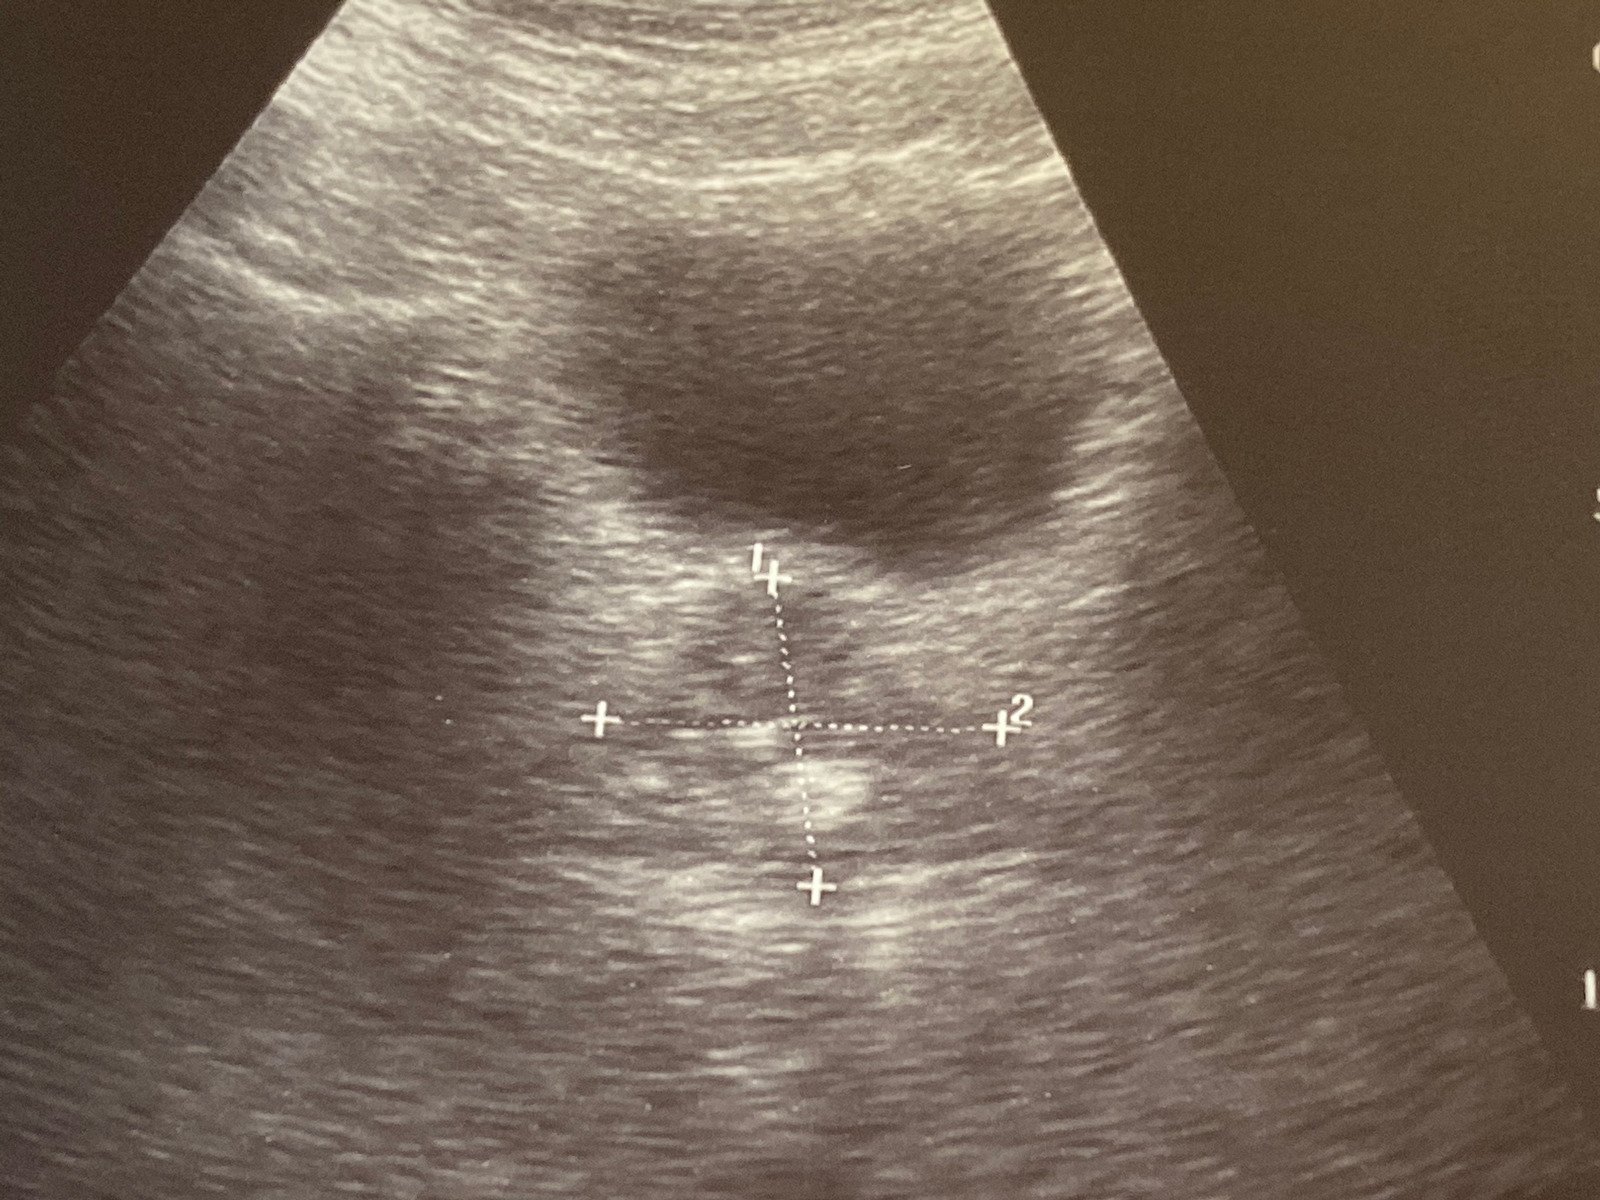

방광 초음파 검사는 방광과 주변 조직의 구조를 비침습적으로 검사하는 진단 절차입니다.

이 검사는 고주파 사운드 웨이브를 사용하여 방광의 이미지를 생성합니다.

방광 초음파는 방광의 크기, 모양, 그리고 주변 조직의 상태를 평가하고, 방광 내 이상 유무를 확인하기 위해 시행됩니다.

검사 과정: 환자는 검사대에 누워서 하복부에 젤을 바르고, 초음파 프로브를 통해 사운드 웨이브가 방광에 전달됩니다.

이 프로브는 환자의 피부를 가볍게 누르면서 움직여 다양한 각도에서 이미지를 캡처합니다.

결과 분석: 초음파 이미지는 방광의 상태를 평가하기 위해 의사에 의해 분석됩니다. 필요한 경우 추가 검사가 권장될 수 있습니다.